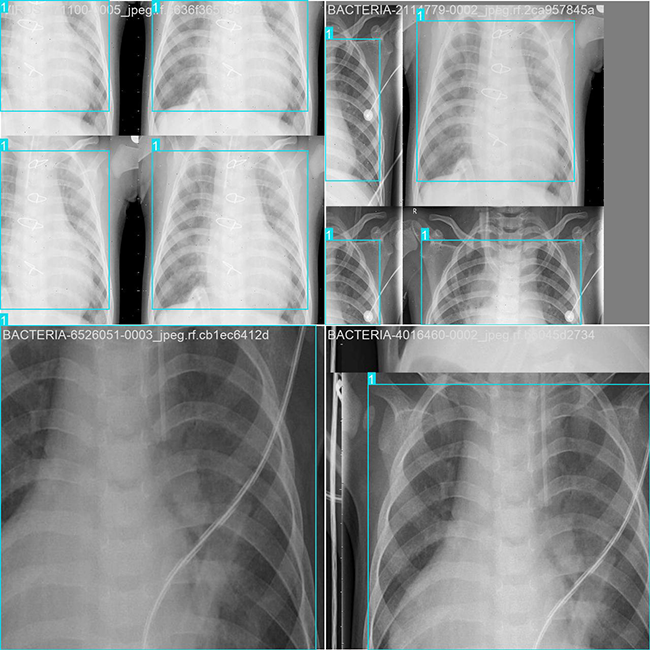

目标检测训练数据可视化

目标检测训练过程中,在数据可视化方面进行了深入研究与实践。模型重点呈现了不同类别的目标物体及其对应的边界框与分类标签情况。经过评估分析发现,在当前阶段该系统运行效果较为理想;然而通过进一步优化数据标注规范并强化模型训练过程中的细节处理环节,则有望显著提升系统的识别准确率以及抗干扰能力